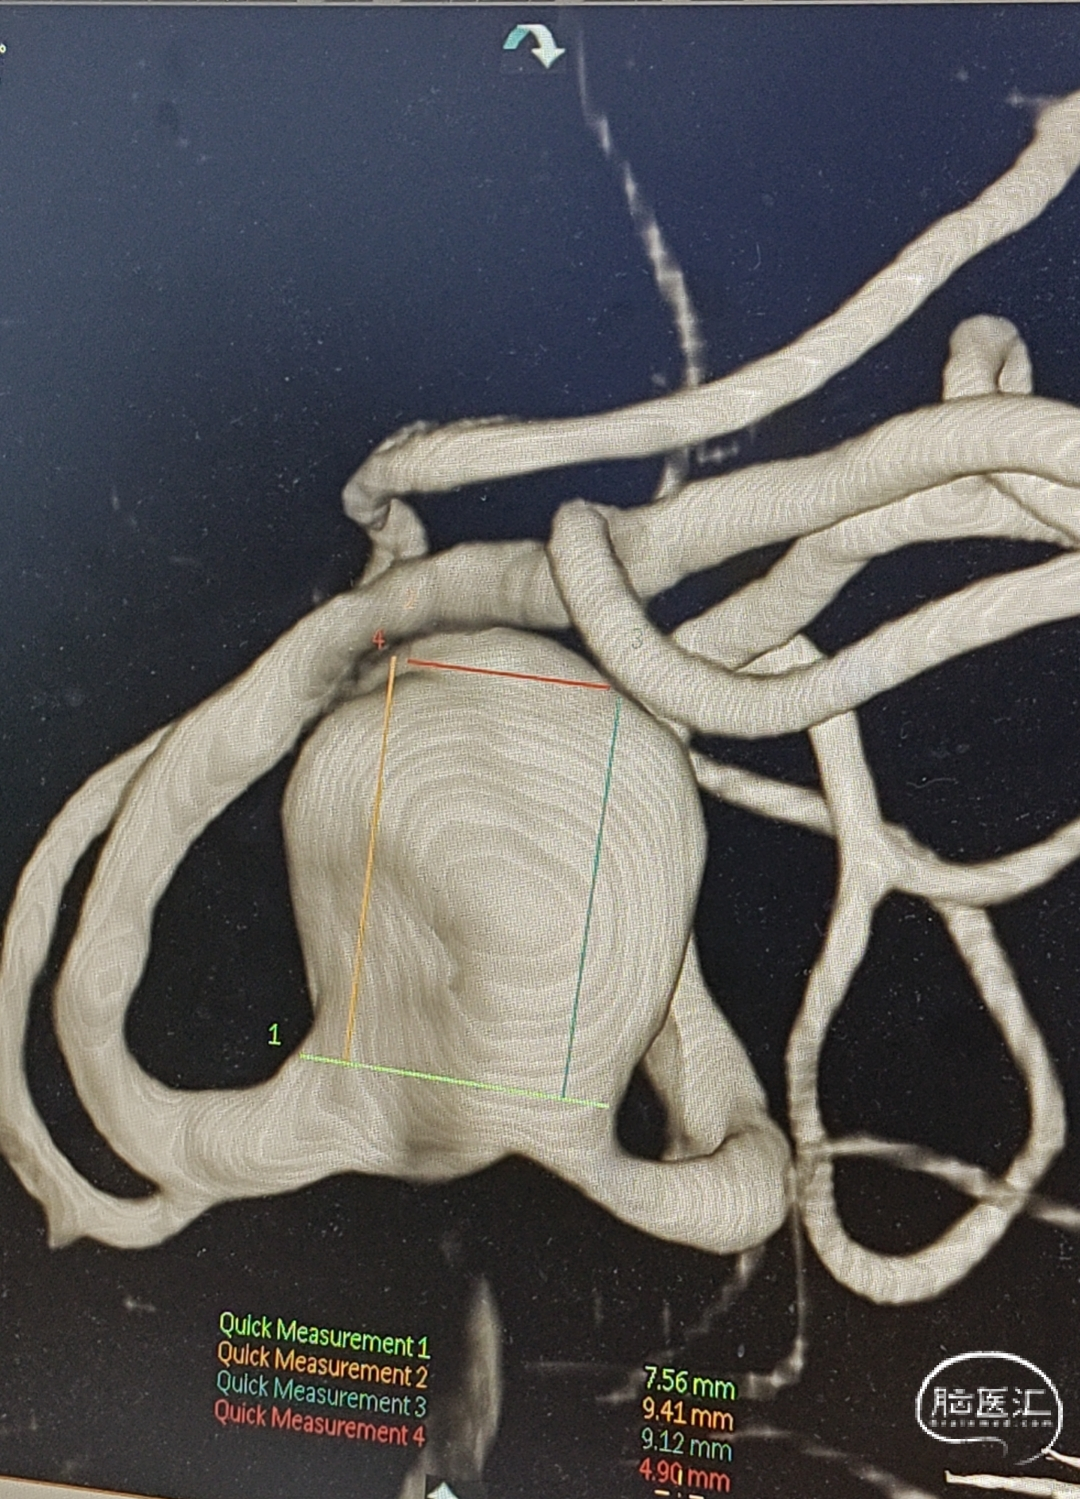

3、辅助检查:头部CTA(外院)提示左侧大脑中动脉M1段分叉处动脉瘤。

术前影像检查

WEB™ SL 11mm*7mm